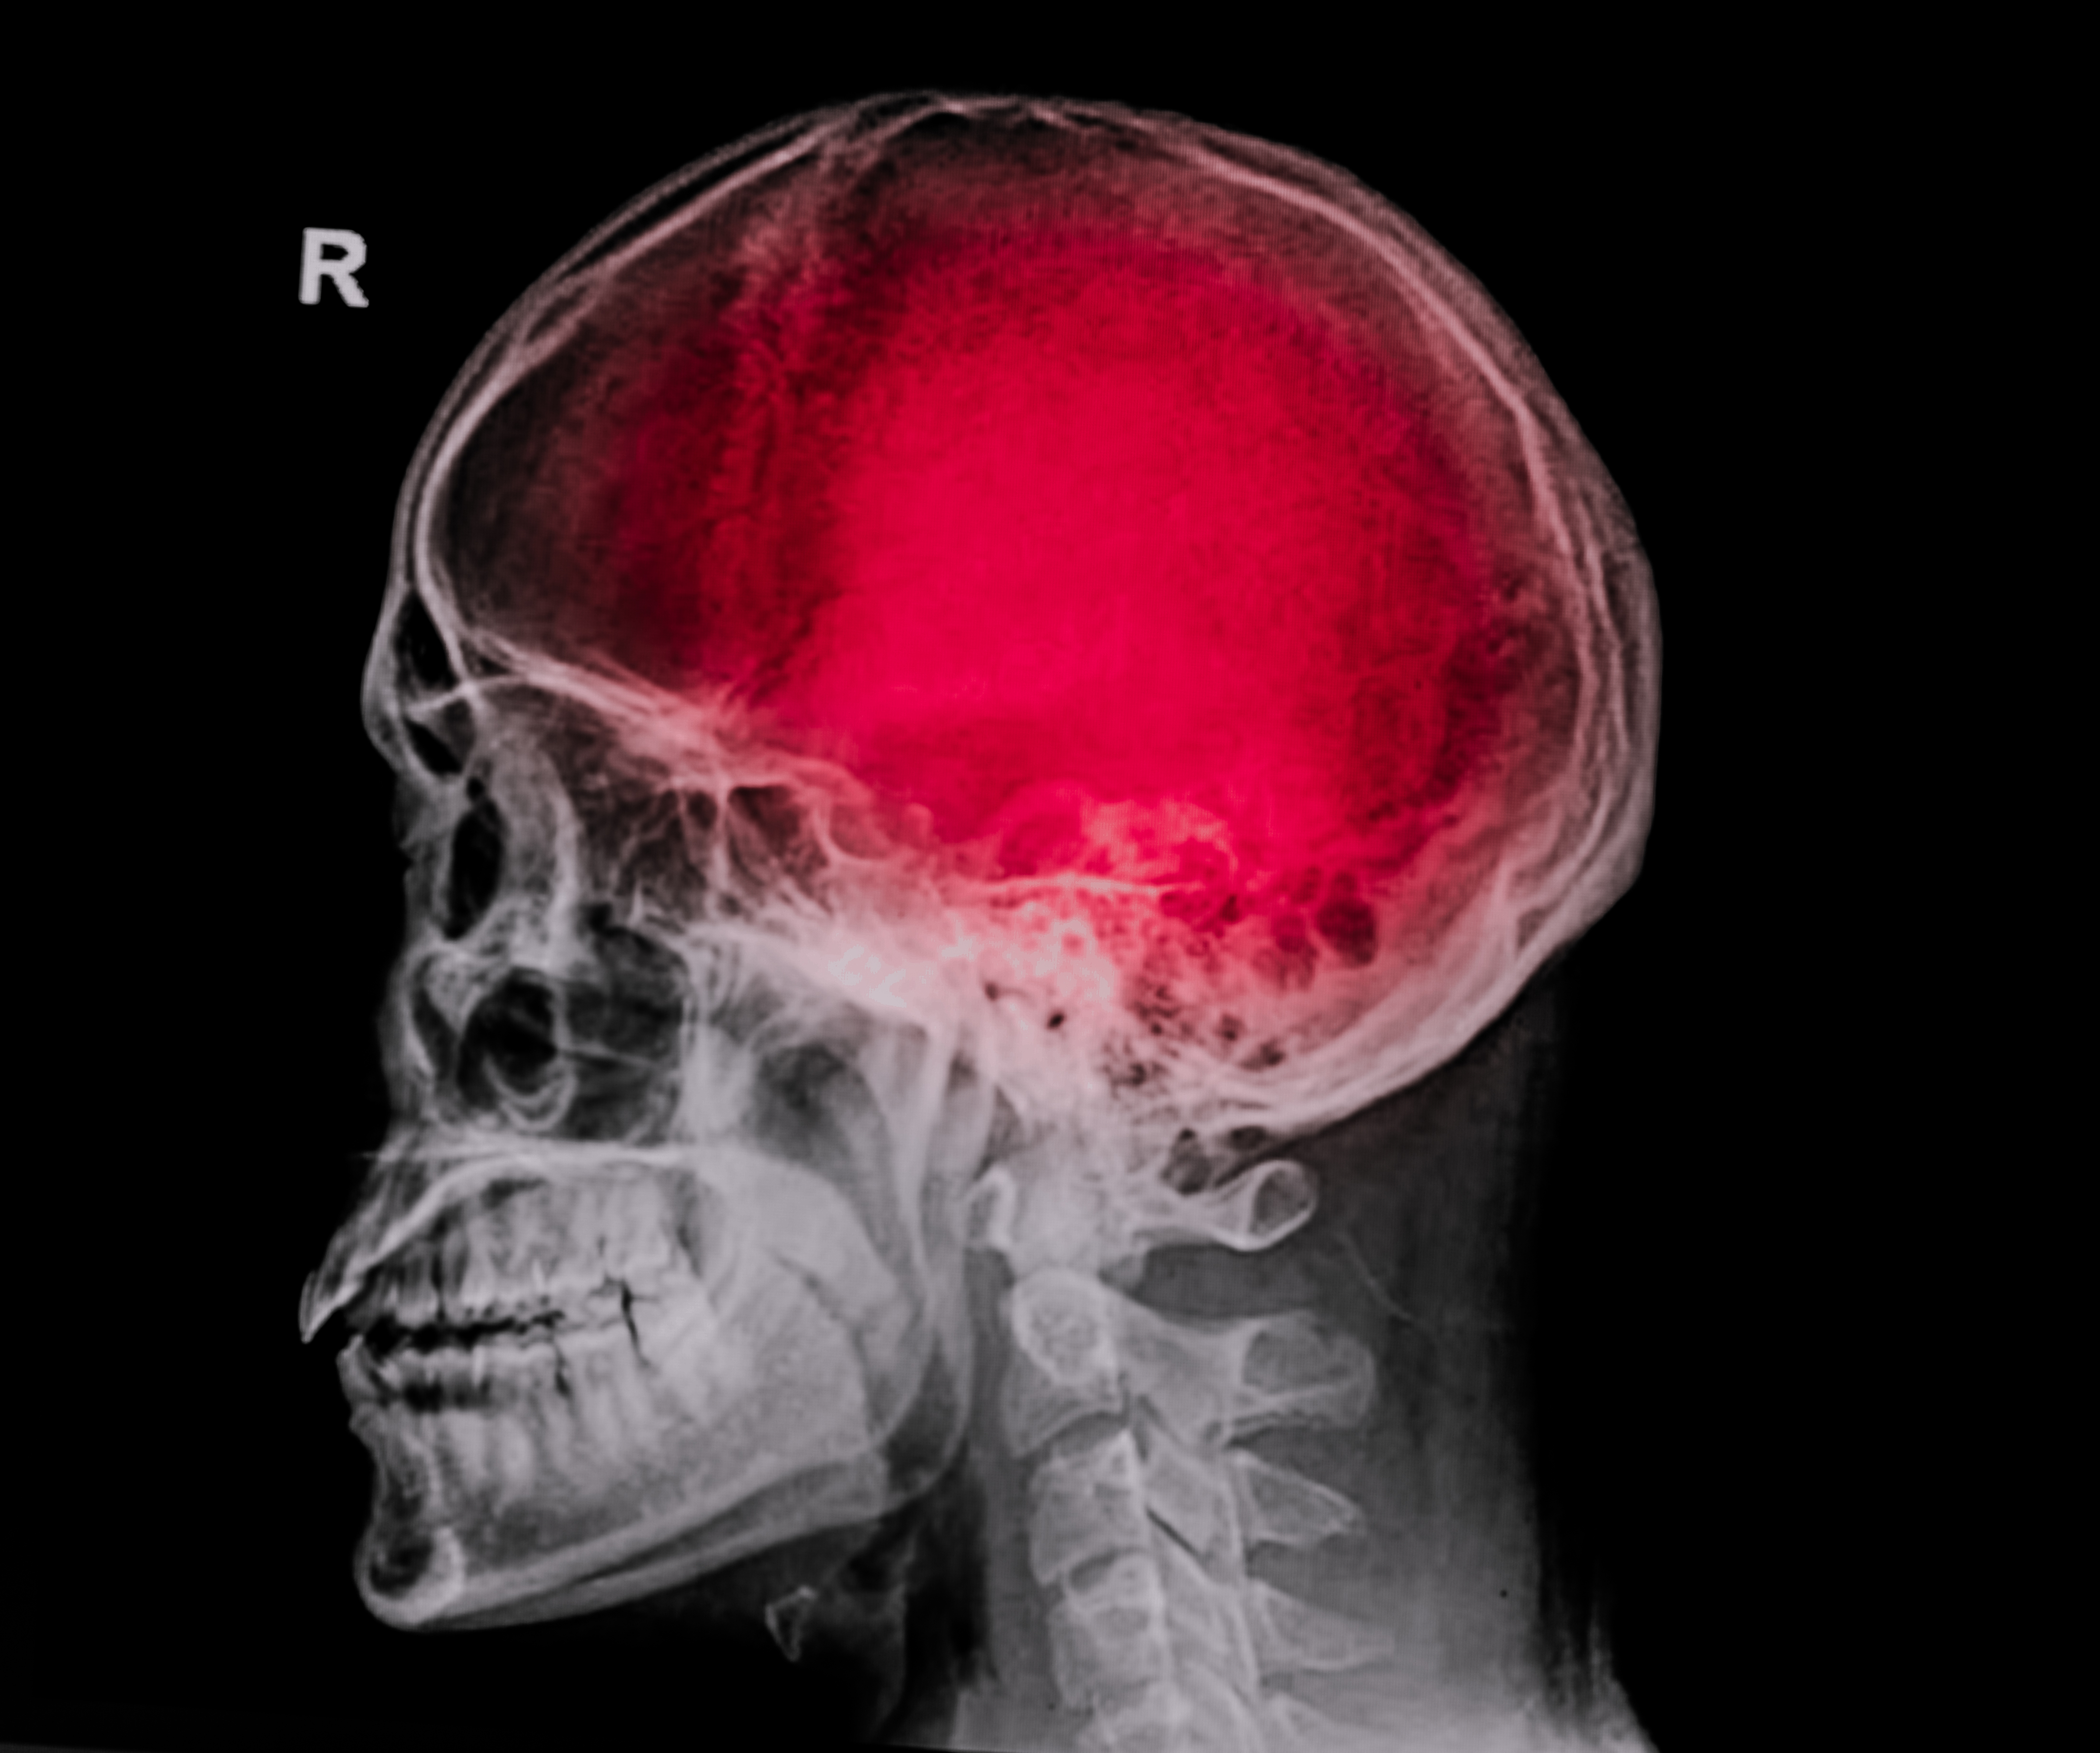

18+ Traumatic Brain Injury Behavioral Changes UK. Traumatic brain injury can happen when a sudden, violent blow or jolt to the head results in damage to the brain. The risk of complications increases with the severity of the trauma.

Children with a brain injury can have the same symptoms as adults, but it is often harder for them to let others know how they feel. As the brain collides with the inside of the skull, there may be bruising of the brain, tearing of nerve fibers and. These types of tbis are serious and can have lasting effects.

Military personnel, football players, soccer players. Always see your doctor if you or your child has received a blow to the head or body that concerns you or causes behavioral changes. Traumatic brain injury (tbi, physical trauma to the brain) can cause a variety of complications, health effects that are not tbi themselves but that result from it. Traumatic brain injuries are categorized the severity of damage to the brain.